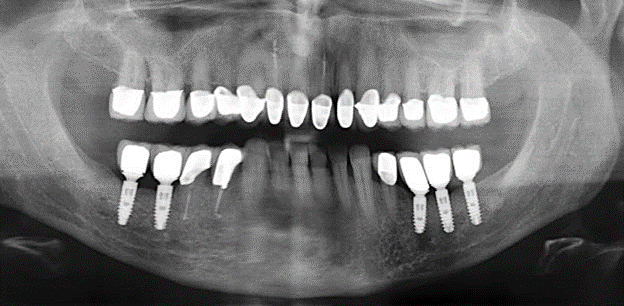

Abb. 1: Panoramaschichtaufnahme des Ausgangsbefundes im Jahr 2004.

Eine 52­-jährige Patientin stellte sich nach Zahnverlust im 3. Quadranten erstmals 2004 vor. Sie hatte den Wunsch nach einer prothetischen Neuversorgung. Im Rahmen der parodontologischen und radiologischen Diagnostik zeigte sich ein ausgeprägter parodontologischer Behandlungsbedarf. Die Zähne 48, 28, 27 zeigten zudem eine infauste Prognose und wurden entfernt (Abb. 1). Nach der erfolgreich abgeschlossenen systematischen PAR­Therapie wurde eine festsitzende implantatprothetische Versorgung mit Insertion von fünf Implantaten in Regio 35, 36, 37 und 46, 47 durchgeführt. Die prothetische Versorgung der natürlichen Zähne erfolgte mit verblendeten Zirkonoxidkeramikkronen, die Implantate wurden mit zweiteiligen individuellen Zirkonoxidabutments und ebenfalls verblendeten Kronen aus einer Zirkonoxidkeramik versorgt (Cercon base colored, Dentsply Sirona Lab). Die definitive Insertion der prothetischen Versorgung erfolgte im Jahr 2005.